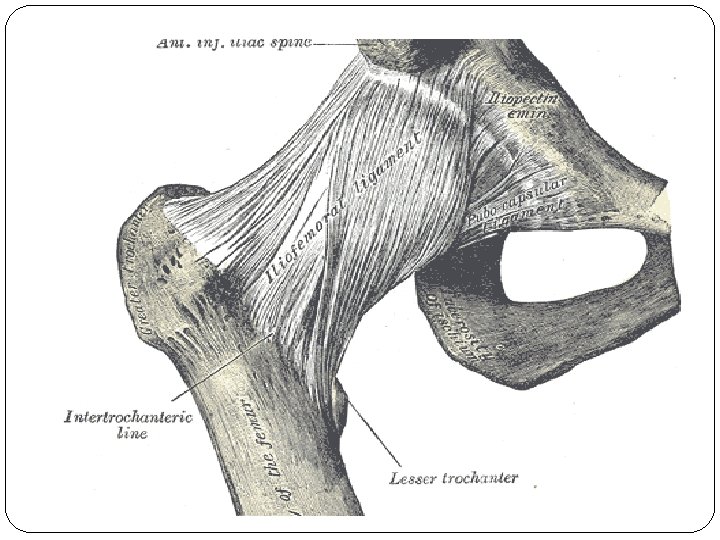

Simple Anatomy The hip is a “ball-and-socket” joint that is held together by ligaments (ligament of teres, ileofemoral, ischiofemoral, transverse ligament). The ball is called the “femoral head” which is the top of the femur or thigh bone. The socket is called the “acetabulum” and is a part of the pelvis. The femoral head fits into the acetabulum creating the hip joint. This joint is normally held tightly in place by the surrounding ligaments and joint capsule.

Cont …. Pathology: a. The acetabulum is shallow (shaped like a saucer instead of a cup). b. The femoral head gets dislocated. c. The capsule is stretched and the ligamentum teres becomes elongated and hypertrophied. Two forms of femoral dysplasia are: Coxa vara, in which the femur head grows at too narrow an angle to the shaft. Coxa valga, in which the angle is too wide.